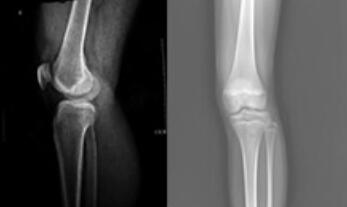

来院后,由王怀庆主任接诊,随后便为她做了详细的检查。X线示:双膝关节边缘及髌骨底呈唇样改变,相应关节面不光整;膝关节间隙呈内窄外宽。确诊:风湿性关节炎。王怀庆主任根据刘女士的病情和身体状况,为其...[详细]